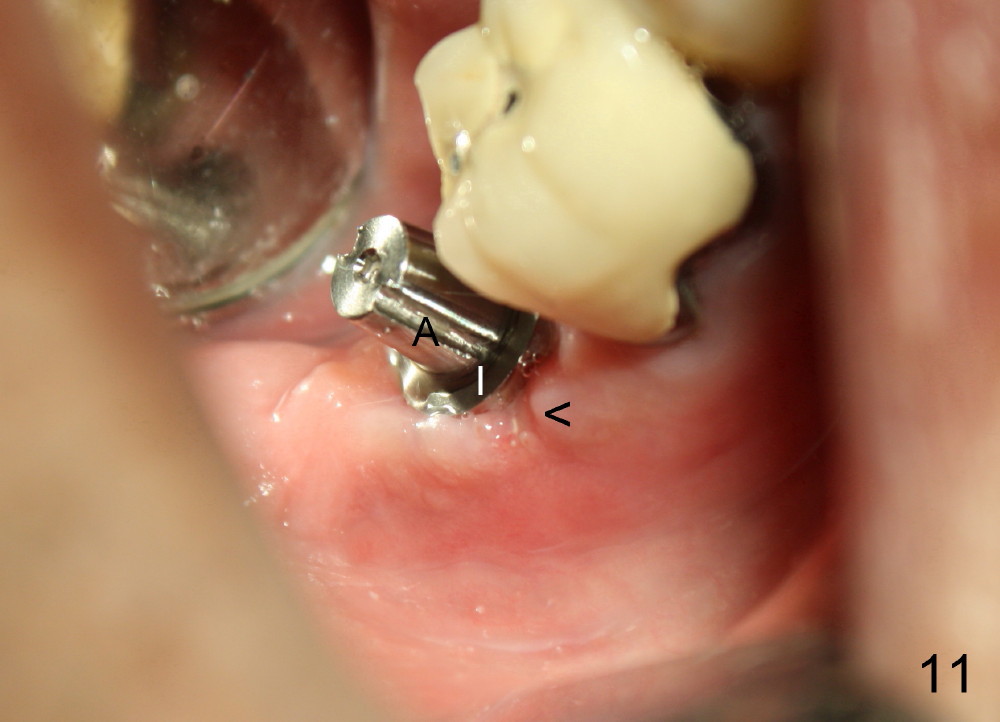

A 51-year-old man has experienced pain and swelling in the lower right 2nd molar for 7 months (Fig.1, P: post in the mesial root; <: gutta percha inserted into a buccal fistula). Fig.2 is taken immediately before extraction (<: purulent discharge from the mesiobuccal fistula) and immediate implant (Fig.3 implant design: 7x14 mm). A vertical root fracture is noted in the mesial root (Fig.4: lingual view). The septum is in fact absent, as compared to Fig.1. The mesiobuccal plate is low; the osteotomy starts lingual to the center of the socket. Fig.5 shows a 4.5x17 mm tap in place: approximately 3.5 mm in the new bone (~2.5 mm from the inferior alveolar canal). When a 7x17 mm tap (14 mm from the gingival margin) is placed in the socket, it looks relatively small. Fig.6 shows a 8x14 mm implant in place with a small gap distally. Mineralized cancellous allograft and Osteogen mixture is placed mainly buccally, followed by a thin strip of collagen dressing and sutures (Fig.7); an abutment (A) is placed to keep perio dressing in place. The perio dressing does not stay long. The buccal portion dislodges by itself 5 days postop. The lingual portion is removed in clinic. New dressing is going to be re-applied, because the buccal wound has not completely healed (Fig.8 <, albeit asymptomatic) with partial exposure of the bone graft (*). Why is the dressing lost so early? The abutment is not long enough; there is plenty of occlusal clearance (Fig.9 arrows). A longer abutment is used to increase mechanical retention for perio dressing (Fig.10). By the time the second perio dressing dislodges, the wound has healed (Fig.11, 13 days postop).